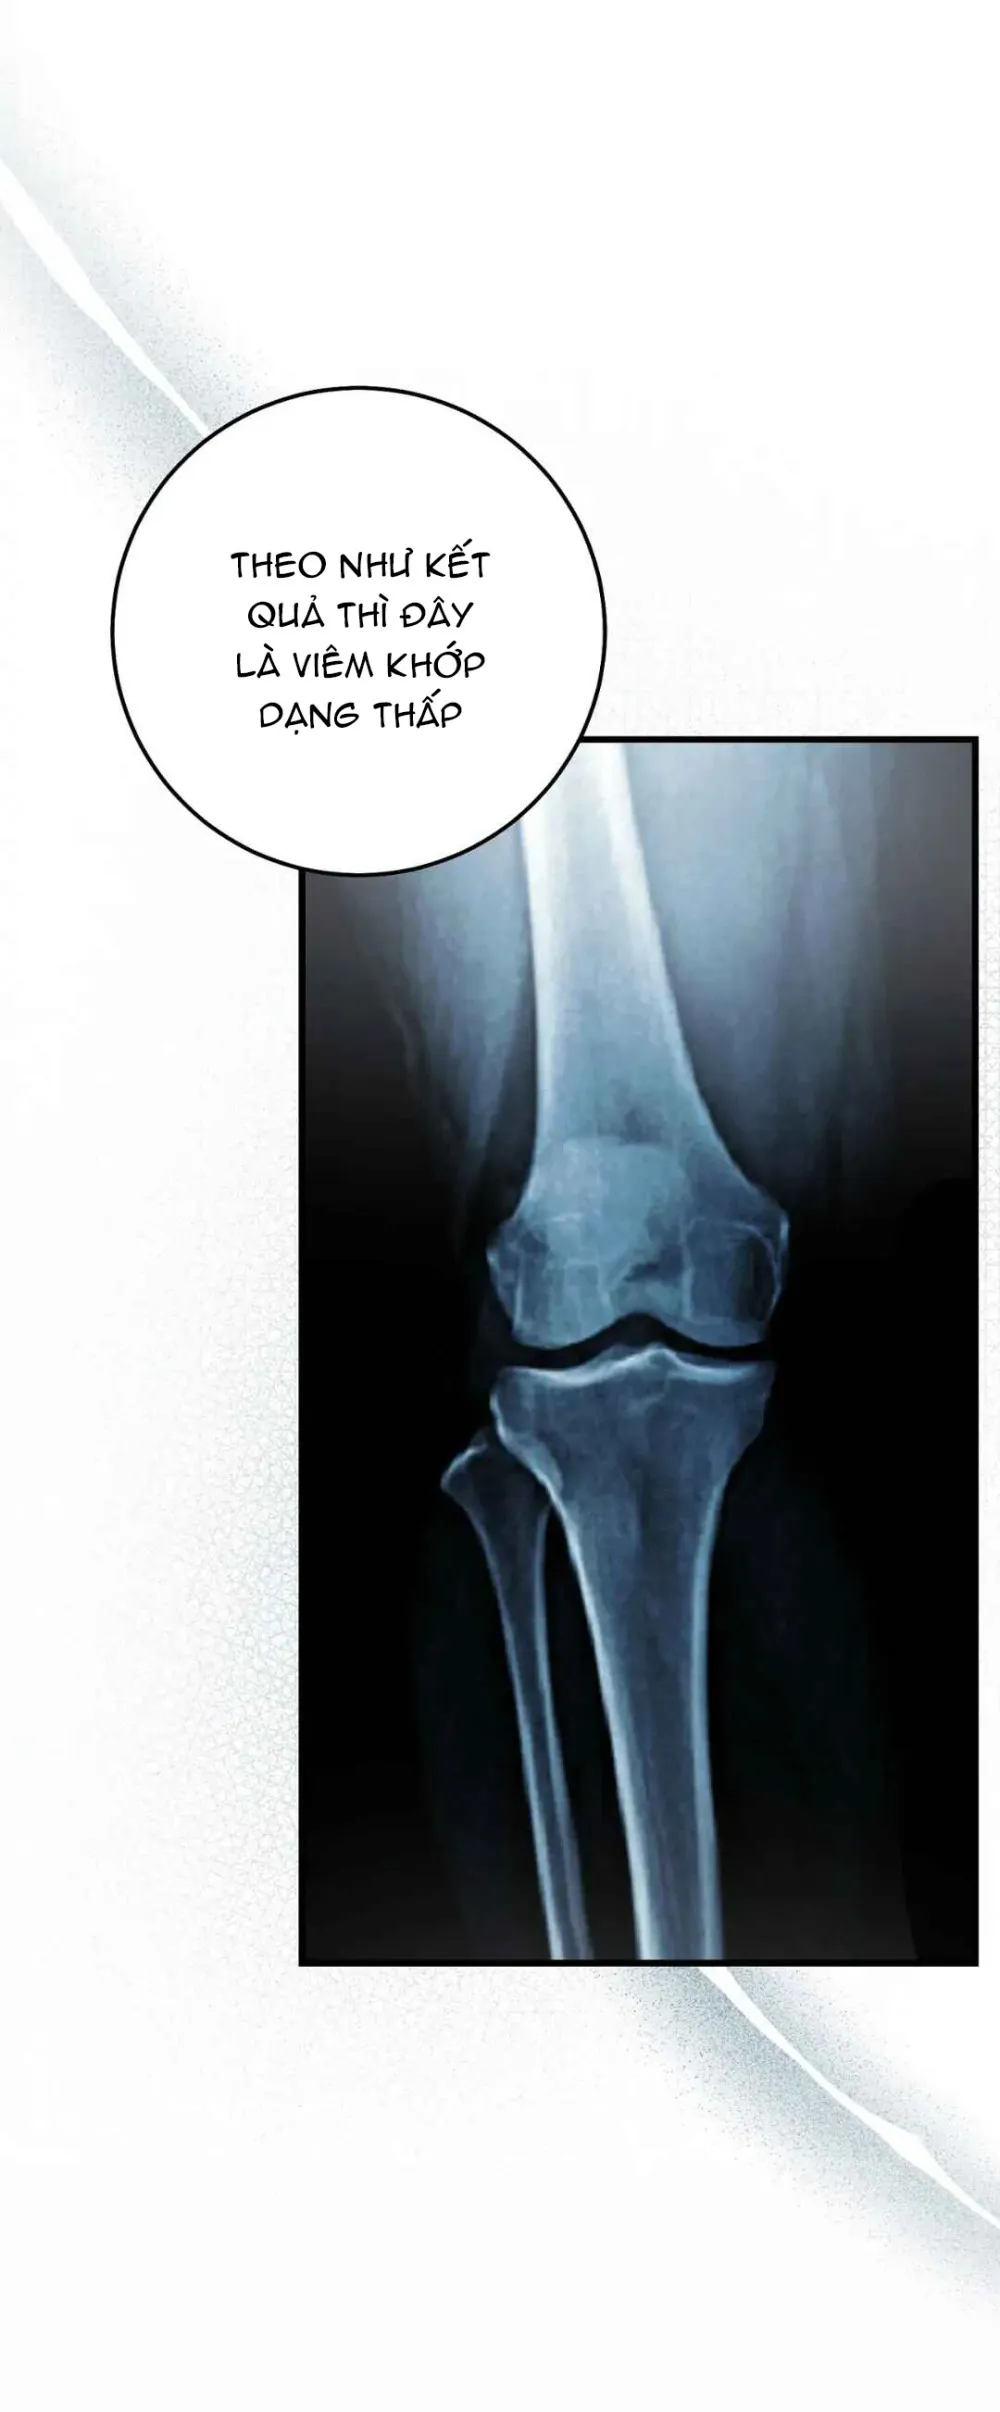

Thợ Săn Muốn Sống Yên Bình - Chapter 28